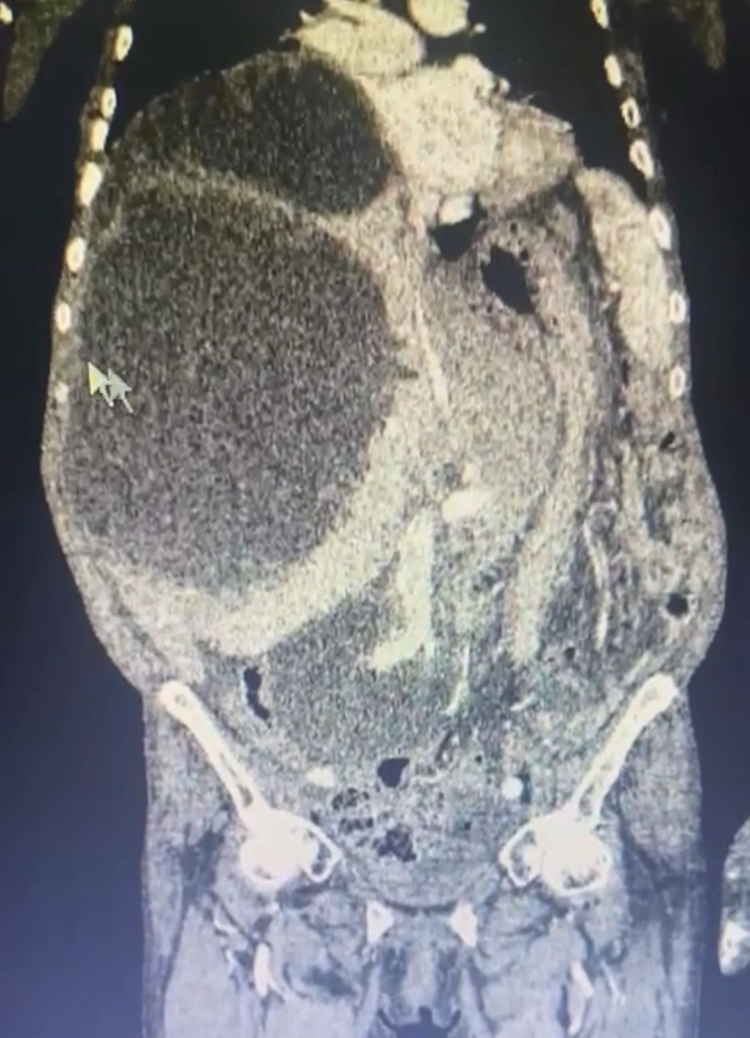

Genel Cerrahi Uzmanı Opr. Dr. İsmet Çelik, Gastroenteroloji Uzmanı Doç. Dr. Aydın Aktaş ve ekibi tarafından yapılan operasyonda 76 yaşındaki Asiye Taşdelen'in karaciğerinde toplamda 90 santimetreye ulaşan 3 ayrı kedi-köpek kisti ameliyatla çıkartıldı.

Kistlerin büyüklüğü dikkat çekerken Genel Cerrahi Uzmanı Opr. Dr. İsmet Çelik, dünya literatüründe tüm karnı dolduran ve 90 santime ulaşan kist görmediklerini belirterek Taşdelen'e yapılan gerekli tetkikler ve görüntüleme sonucu karaciğerinde üç adet kedi-köpek kisti (hidatik kist) tespit ettiklerini ifade etti. Çelik, başarılı geçen ameliyatın ardından hastanın sağlık durumunun iyi olduğunu ve sürecin yakından takip edildiğini belirtti.

Dünya literatüründe tüm karnı dolduran ve 90 santime ulaşan kist görmediklerini ifade eden Çelik, "Asiye Hanım, maalesef ihmal edilmiş bir hastamız. Bu kist, kedi ve köpeklerin dışkısı ve yediği yiyeceklerle bulaşan bir hastalık. Bu kist, genellikle tesadüfen yakalanabilir. Karaciğere yerleşir. Bu hastamızda da durum öyle olmuş. Ameliyat olamayacağı söylenip eve yollanmış. Bizler detaylandırıp ameliyat kararı aldık. Hastamızın karaciğerinde 3 ayrı kist vardı. Tüm karnı kist ile kaplıydı. 2 tanesinin tamamına çıkardık. Diğerini ise kontrolle alarak içini boşalttık. Dünya literatüründe tüm karnı dolduran ve 90 santime ulaşan kist görmedik. Ameliyatımız 2 saat sürdü. Hastamızın safra yolları kontrol edildi. Hastamızın durumu gayet iyi. Solunum cihazından bağımsız olarak kendi başına solunum yapabiliyor. En korktuğumuz şey; alerjik bir durumun olması. 90 santim çapındaki kist vücuda yayıldığı zaman alerjik bir durumda hastanın ölümüne sebep olabilmesi. Göremediğimiz yayılımlar için tedbir alıyoruz" diye konuştu.